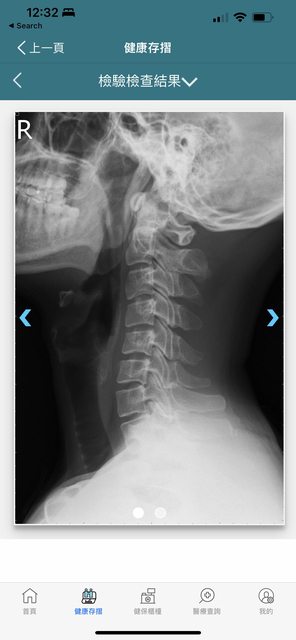

- 頸椎 X 光 似乎不太正常 https://i.imgur.com/cVkB5ca.jpg